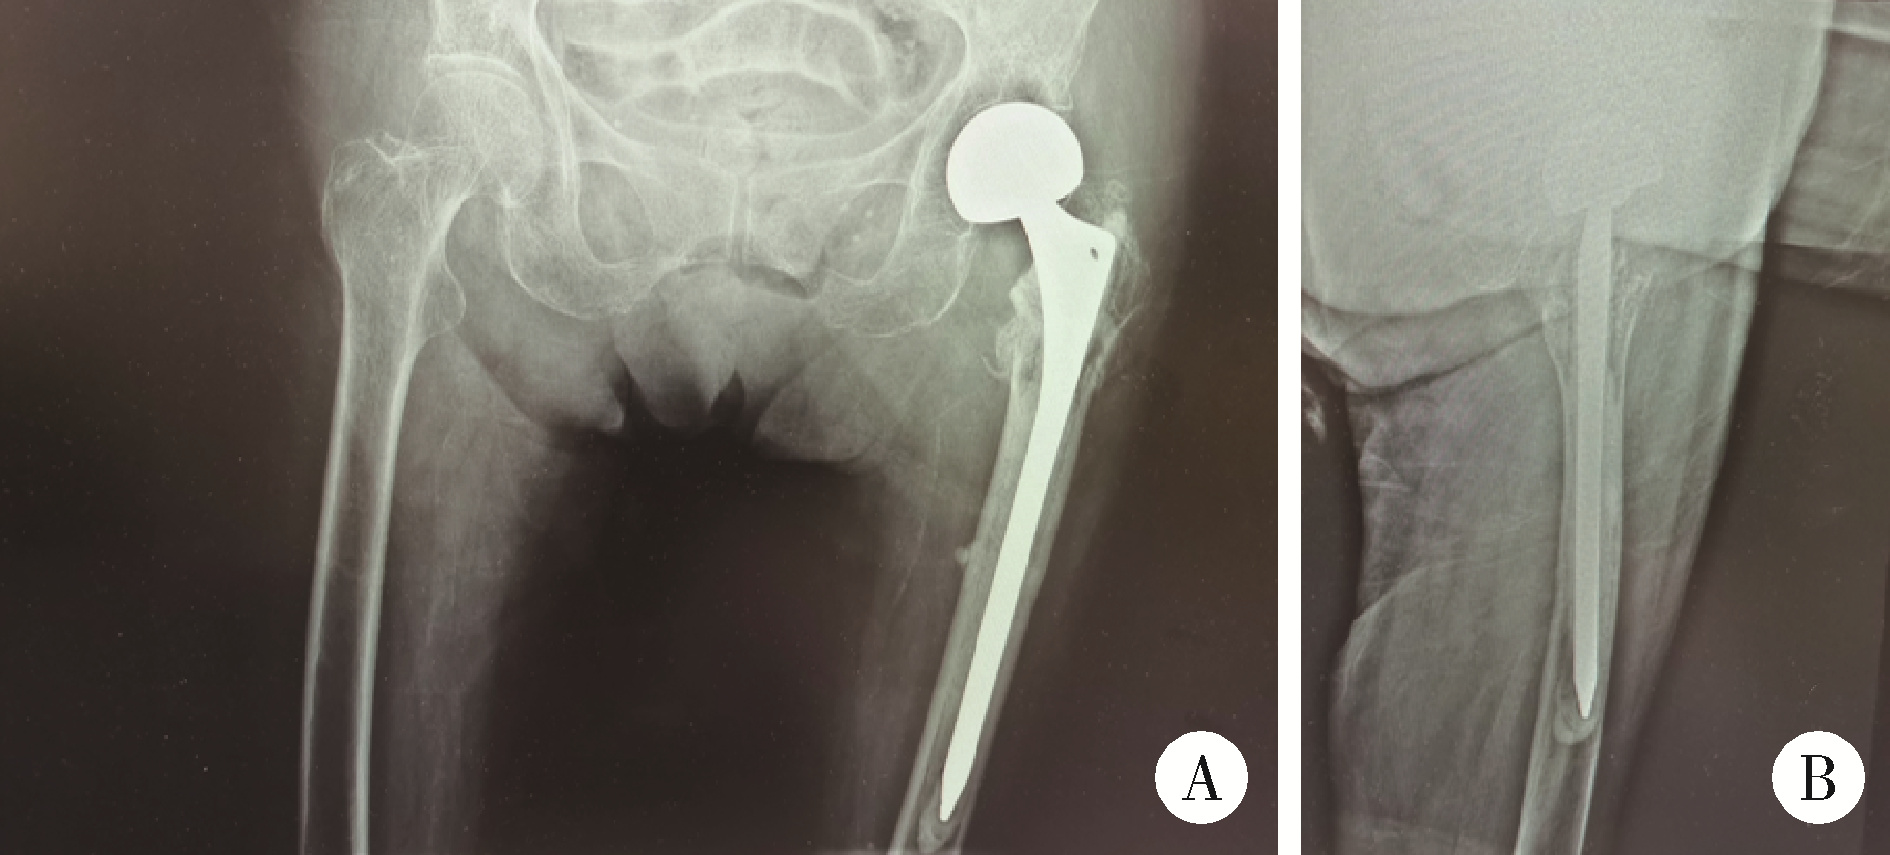

eb4acaabee778636e6a97f8010df93。大腿骨頸部骨折の手術【手外科・外傷】 | おおさかグローバル。Frontiers | Impact of Periosteal Branches and Septo。「大腿骨近位部骨折 : 大腿骨頚部・転子部・転子下骨折の手術手技」高平 尚伸 / 最上 敦彦 / 神田 章男 / 北田 真平定価: ¥ 14000#高平尚伸 #高平_尚伸 #最上敦彦 #最上_敦彦 #神田章男 #神田_章男 #北田真平 #北田_真平 #本 #自然/医療・薬学・健康 サージカルテクニック裁断済みです。裁断にご理解頂ける方のみご購入よろしくお願いします。Treatment of moderate and severe hallux valgus by performing。書き込みは見たところございません。ペリー 歩行分析 正常歩行と異常歩行。アシックス やり投げ ジャベリンプロ3。